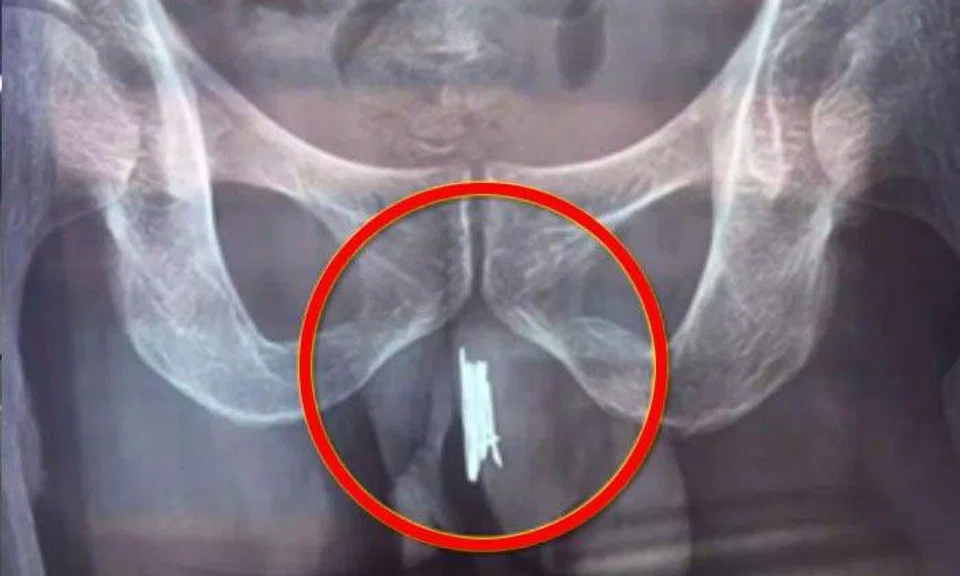

A man in Shenyang, China, was forced to seek medical help after he shoved no less then 15 needles up his private parts.

Throughout the past year, he had been putting sewing needles up his urethra, some of which have started to rust before they were removed from his urinary tract.

Thankfully, doctors managed to successfully remove the foreign objects.